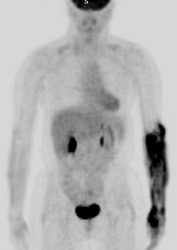

Hyperinsulinemia: The patient below had

a normal glucose level and was injected for an FDG PET

scan. Imaging revealed intense cardiac uptake and a large

about of muscular activity. The findings are consistent

with a hyperinsulinemic state and the patient subsequently

admitted to eating a small breakfast. |